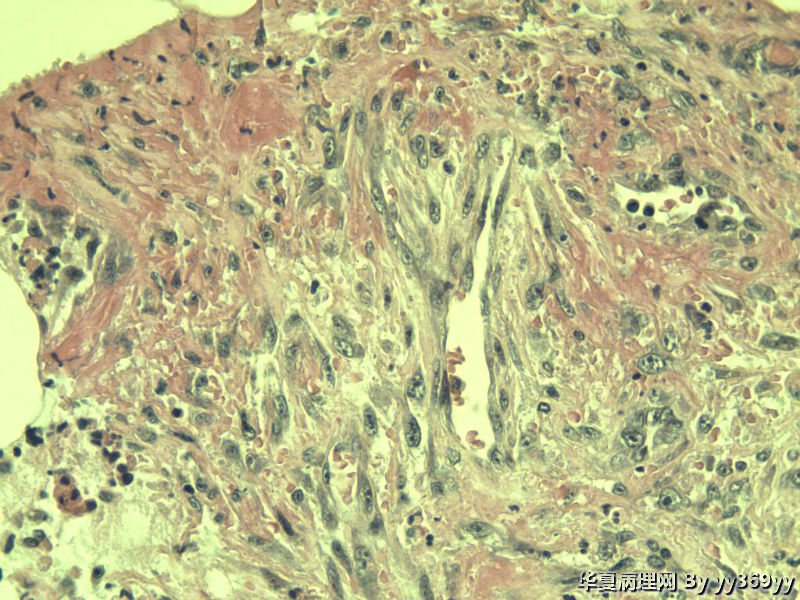

男 30岁 小肠一段,肠管严重粘连可见一体积为 2.5 × 2 × 1.5 cm3的肿块,切面灰白,实性,质中

小肠肿瘤图1

名称:图1

描述:a553.Jpg

恶性肿瘤   淋巴瘤 脂肪肉瘤  低分化腺癌 做IHC

从最后这几张高倍镜图看,淋巴样细胞弥漫性增生,很可能是淋巴瘤。

只是倒数那几张是取自淋巴结吗,还是所有的? 考虑恶性GIST,做IHC

倾向良性的,像炎性肌纤维母一类,需要排除GIST,期待学习~~~

考虑炎性肌纤维母细胞瘤、炎性纤维性息肉、胃肠间质瘤,不考虑淋巴瘤